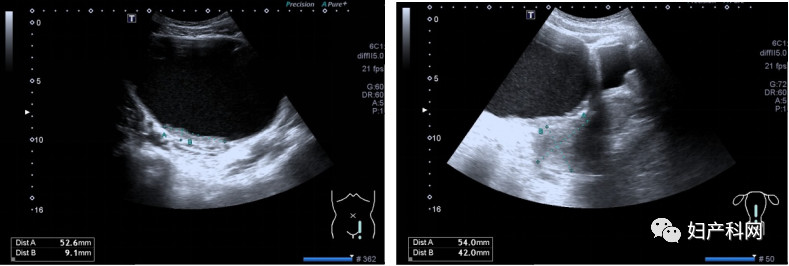

2019-06-30本院经腹子宫附件超声检查示:子宫后位,正常大,内膜厚0.64cm(双层)。宫壁回声均匀。右卵巢正常大,回声无殊。左卵巢显示不清。子宫上方见一巨大囊性回声,上达脐上五指,双侧达腋前线,内液尚清,囊壁上见数个稍强回声,较大5.3*0.9cm,内未及明显血流信号。诊断结果:子宫正常大,子宫上方巨大囊性块,建议进一步检查。